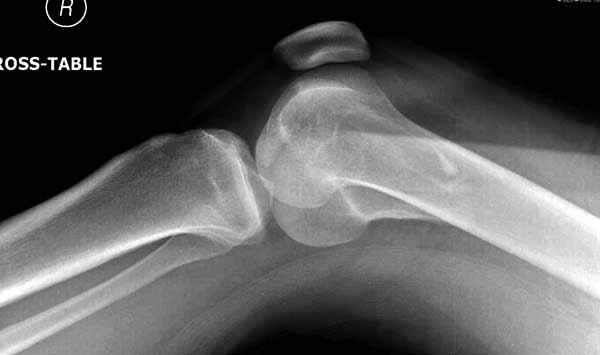

Антеградное штифтование не очень годится при переломах типа C3, когда есть многооскольчатость именно суставной поверхности. А при переломах типа C1 и С2, т.е. и в обсуждаемом случае тоже, он как раз вполне оптимален. На межфрагментарную компрессию как-то не приходилось так драматически полагаться при интрамедуллярном остеосинтезе, результаты хорошие без нее были.

В этой терминологии мы, получается, создавали компрессию встречными спицами с упорами или reduction clamps, а потом вполне обходились запирающими винтами как позиционными. Бывает, проводим 1-2 спонгиозных винта 6,5-8 мм - вот они вполне компрессирующие.

И уже лет шесть мы используем возможность ввести в дистальное овальное отверстие 3 винта, которые именно запираются в этом отверстии, не люфтят, а обеспечивают угловую стабильность - см картинку.

Получается и стабильно, и очень дистально, нижний край отверстия в 3 мм от дистального конца гвоздя.

Рационально ориентироваться на качественный аспект - проблема или решается, или нет. Переломы типа 33C1 или C2 (то есть без фронтального раскалывания мыщелков, как на показанной Вами томограмме) при обычном качестве кости успешно можно фиксировать гвоздями с фронтальными винтами. Получается, их прочностных характеристик уже достаточно.

В приложении пример недавней операции, C3, открытая репозиция, фиксация мыщелков спицами и винтами, ретроградный синтез большеберцовым гвоздем 10,5 мм диаметром, винты 5 мм.

Позволю себе напомнить коллегам ещё раз, что являюсь сторонником антеградного остеосинтеза при переломах дистального эпиметафиза бедренной кости. Такая приверженность основана не на преимуществах внесуставного введения стержня или большем проценте положительных результатов. Она основана на возможности обеспечить блокирование на минимальном расстоянии от суставной поверхности в нескомпрометированной кости и, таким образом стабилизировать максимально низкие переломы. В приведенном Вами случае самый дистальный из блокирующих винтов проведен на расстоянии более 2 см от конца стержня. Из-за того, что к стержню присоединяется кондуктор, на стержне теряется 1-1,5 см его длины, где можно было разместить отверстия для блокирования. И что более важно, вместе с потерянной для этой цели длиной стержня утрачивается для размещения блокировочных винтов, пожалуй, самая ценная часть дистального эпиметафиза бедренной кости. Проблемы дистального блокирования в разных плоскостях, локализации точки ввода стержня при антеградном остеосинтезе – это всё решаемые технические проблемы. Но антеградный остеосинтез низких дистальных переломов бедра при адекватном блокировании в нескомпрометированной кости обеспечивает решение стратегической задачи – стабильный остеосинтез и возможность нагрузки.